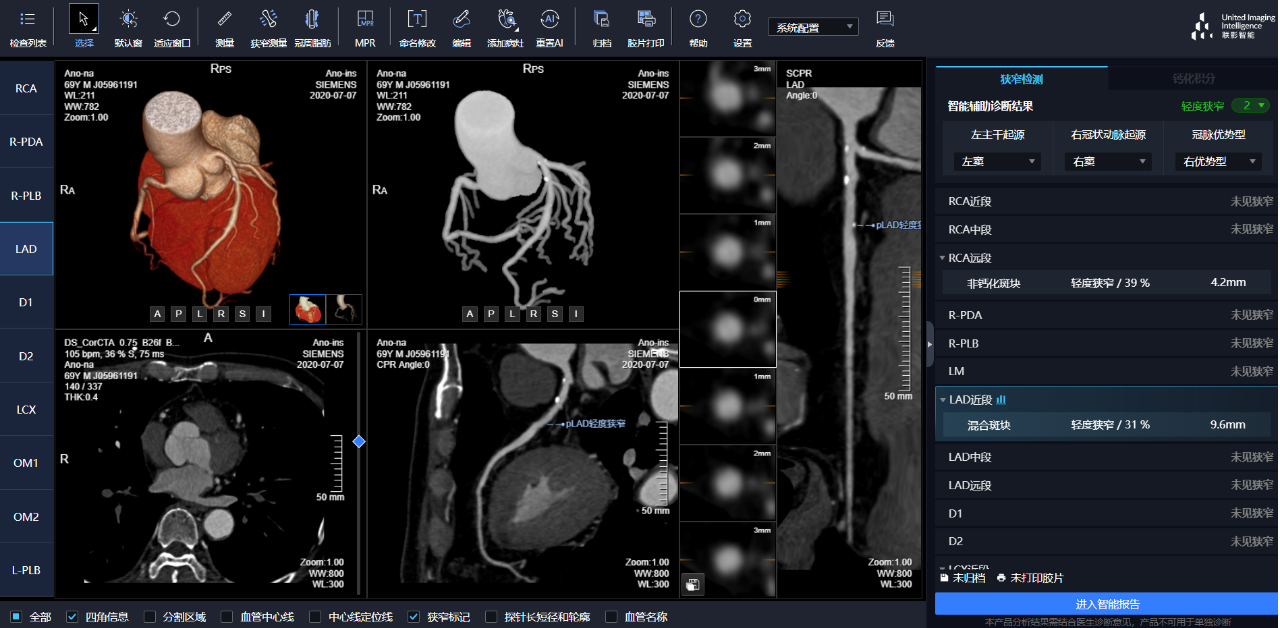

相較于傳統(tǒng)人工閱片,在聯(lián)影智能AI軟件的輔助下,640CT閱片的靈敏度和閱片效率均有顯著提升,對于細(xì)微骨折乃至于隱匿性骨折的判斷,準(zhǔn)確度更高,極大地減少了漏診及誤診。

通過3D視圖可任意旋轉(zhuǎn)觀看血管全貌,AI秒級(jí)實(shí)時(shí)計(jì)算重建血管,可實(shí)現(xiàn)多維輔診包含:板塊定性定量分析、狹窄評估、心肌橋檢出、支架檢出、鈣化積分,全程AI關(guān)注心血管健康。